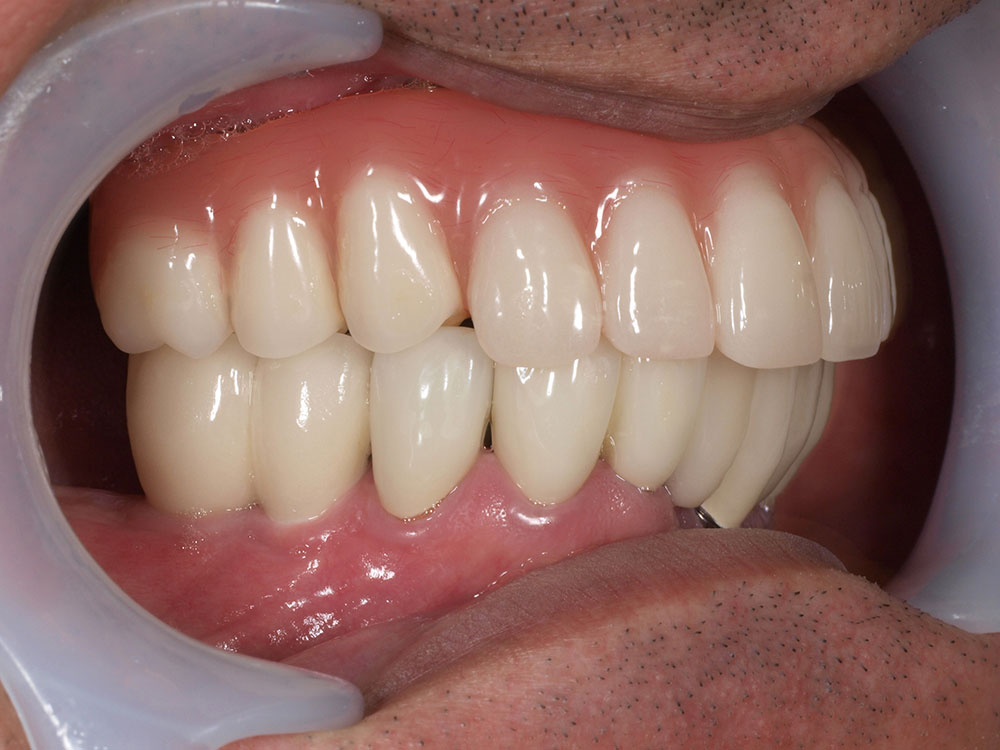

症例紹介

- 主訴

- 入れ歯が合わない。食べにくい。人生を豊かにしたい。

- 処置内容

- 上顎4本で12歯(オールオン4)、下顎4本5歯。

上下抜歯即時埋入、即時荷重(手術当日にインプラントの上に仮歯装着)

- 治療費用

- 上顎:約290万(税込)、下顎:約210万円(税込)

- 治療期間・通院回数

- 上顎:9か月/9回

下顎:6か月/7回

- リスク

- 術後の腫れ、痛み(ピークは3日後、1週間で軽減)

上部構造物、仮歯の破折、人工歯根脱落リスクがあります